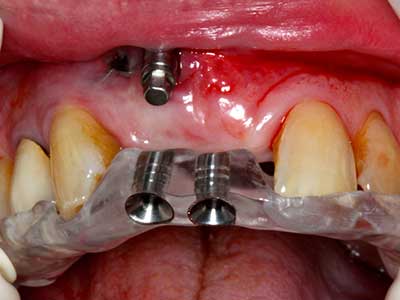

Fig. 13: En este paciente de 52 años con una anchura del hueso residual del maxilar inferior de 4 mm, hay que asegurarse de que exista refrigeración por agua adecuada durante la partición del hueso.

Fig. 14: Incorporación de cuatro implantes RSX cónicos (Bego Implant Systems, Bremen).

Fig. 15: El control radiológico realizado al cabo de un año muestra una estabilidad del nivel óseo.

Fig. 16: También condiciones intraorales estables con incorporación de los implantes en la encía queratinizada.

Fig. 17: Tomografía computarizada de un osteoma de crecimiento progresivo ...